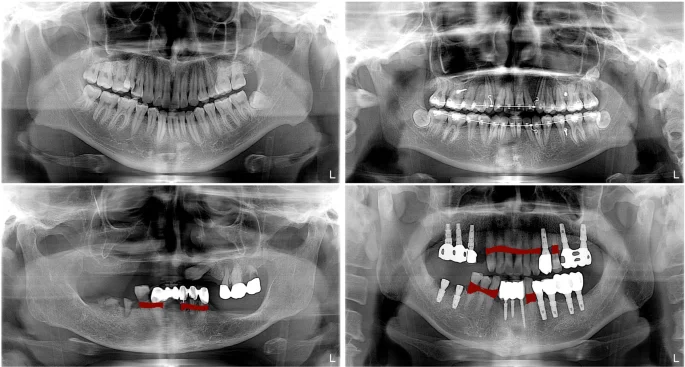

1️⃣ 치아 상실 후 오래 방치된 경우

치아를 잃은 후 시간이 지나면

잇몸뼈는 자연스럽게 흡수됩니다.

이 경우 임플란트를 지지할 뼈가 부족할 수 있습니다.

특히 수년내 최대 50%까지 흡수되기도 합니다.

2️⃣ 잇몸뼈 흡수가 심한 경우

풍치가 진행되었던 부위는

이미 골 손실이 상당한 경우가 많습니다. 이경우, 뼈이식을 통해 물리적으로 지지할수 있는 뼈 회복하는 것이 필요합니다.

Kim et al, DeNTNet: Deep Neural Transfer Network for the detection of periodontal bone loss using panoramic dental radiographs, 2019

3️⃣ 상악동과의 거리가 부족한 경우

특히 위 어금니 부위는

상악동과의 거리 확보가 중요합니다.

Lucas et al, Evaluation of the Maxillary Sinus of Patients with Maxillary Posterior Implants: A CBCT Cross-Sectional Study, 2022